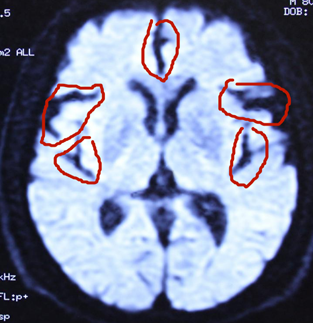

杜先生阿尔茨海默症典型病例治愈简介: 2018年8月30日接诊。接诊地点:北京石景山八大处中西医结合医院贾学铭教授诊室。 患者:杜先生,男,80岁,经常头晕不舒10余年,近二年多病情加重,出现记忆障碍渐渐加重,对事情过后即忘,每天早上下楼买去3-4次买同一种报纸,买后放下过会又去买,别人让他不要买了,过后又去买回来了,对其他刚刚放下的物品回头即忘,对其他人的名字或数字经常记不清等,经北京多家大医院诊断为:阿尔茨海默症,经过多种方法治疗无效。从网上查到而来要求治疗,自带北京世纪坛医院核磁共振2018年8月29日片显示:脑萎缩(严重)。接诊后给以纯中药治疗4个多月,头晕不舒消失,记忆恢复正常,还能很正常的照顾他人,症状全部消失。2019年1月2日又到北京世纪坛医院作核磁共振片显示:脑萎缩与前片比较明显恢复。治疗结果:阿尔茨海默症完全治愈。以下是核磁共振片治疗前后的对比: 杜先生阿尔茨海默症治愈前后拍核磁共振片比较,要观察细节:

2018年8月29日前见片治疗脑萎缩严重。病情严重。 2019年1月2日治疗后见片脑萎缩减轻。病情治愈。 脑组织逆生长的情况见左右两个图内红圈相对等部位的比较,圈内白色的部分是脑组织,圈内黑色的部分是没有脑组织了是萎缩后空缺的现象,黑色越多脑萎缩越严重,白色越多脑组织越多,脑组织多了,就是改变了脑萎缩,就是脑组织逆生长,因此,通过中药使脑组织逆生长就消除了和治愈了脑部的疑难病。该患者的阿尔茨海默症通过纯中药达到了脑组织逆生长,患者的记忆障碍就正常了,病情就治愈了。 实践证明阿尔阿尔茨海默症的发病,不仅是现代医学认为的海马体萎缩的问题,是脑部整体出现了问题,也不是不可治愈的疾病,是能够治愈的。我们经过几十年的研究探讨创新,用纯中药治愈阿尔茨海默症是科学的真实有效的,是现实的!只要是脑组织逆生长,阿尔茨海默症就必然能够治愈。

杜先生核磁共振片其中单图的治疗前后比较: